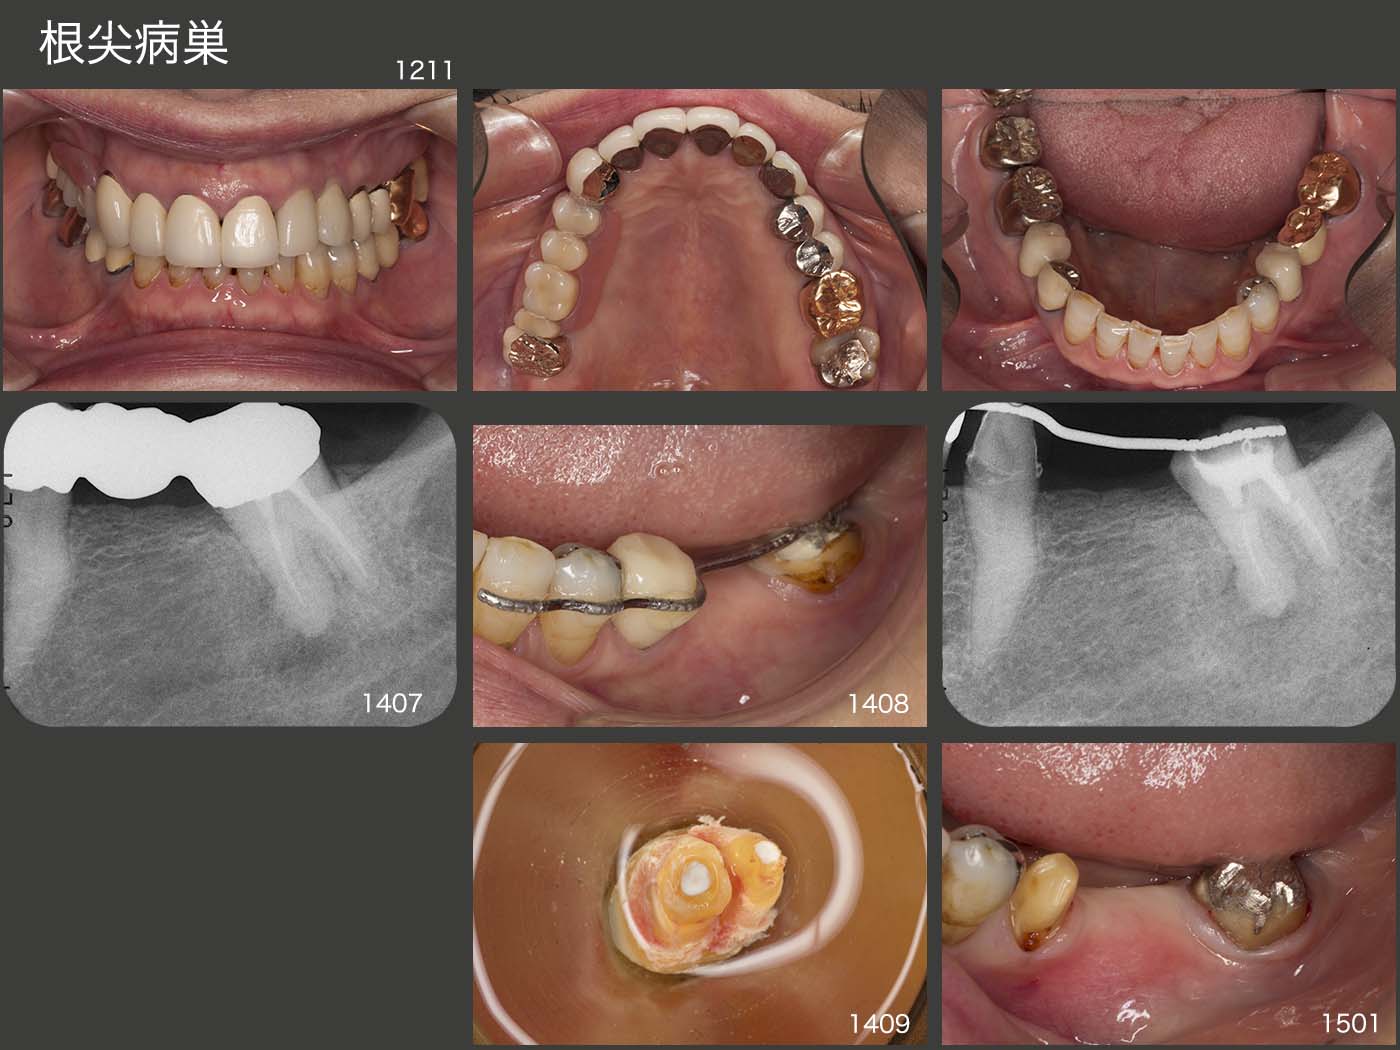

1999年初診、55歳女性。スライド上段3枚は、2012年11月の状態。2014年6月、夜間就寝時に左下7に痛みが出たとのことで来院した。デンタルX線写真に以前から根尖病変がみられたが、咬みしめの可能性も否定できず、暫く様子をみてもらった。しかし、7月に激痛が生じ、これは根尖病巣による急性症状と診断した。抗生剤を投与したのち感染根管治療を数回行ったが、根管が閉鎖しており内科的な治療は不可能と診断した。そこで8月、まず3週間にわたり、左下7の矯正的挺出を行い、抜歯しやすいように細工した。9月、歯の動揺を確認したのちに抜歯を行い、口腔外でスーパーボンドにより根尖を封鎖した。直ちに元の場所に戻し、隣在歯と3週間固定した。3ヵ月経過を観察し、補綴処置に移行した。